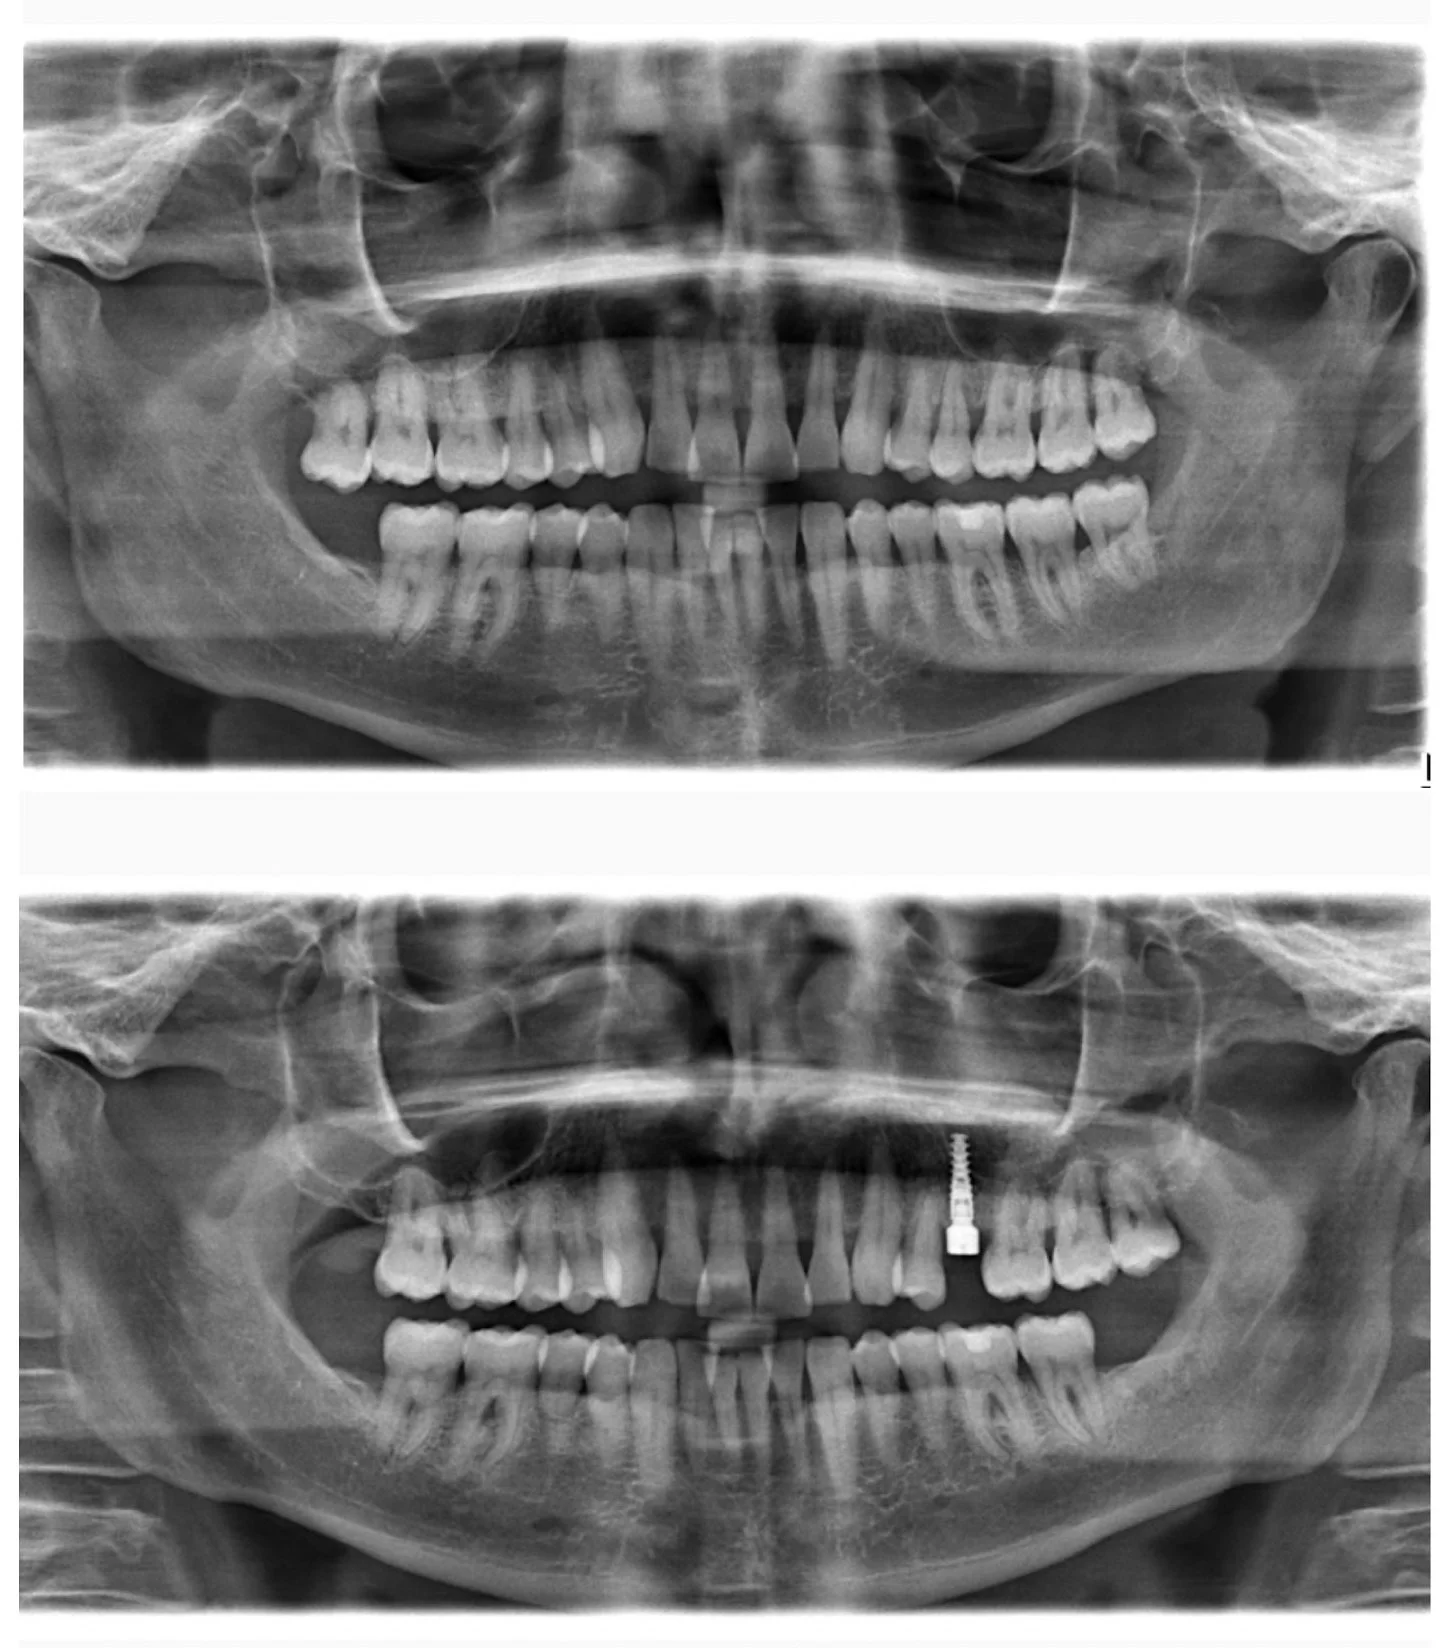

Implant planning

Implant placement

Extraction of tooth and placement of immediate implant

Implant Planning with CBCT imaging